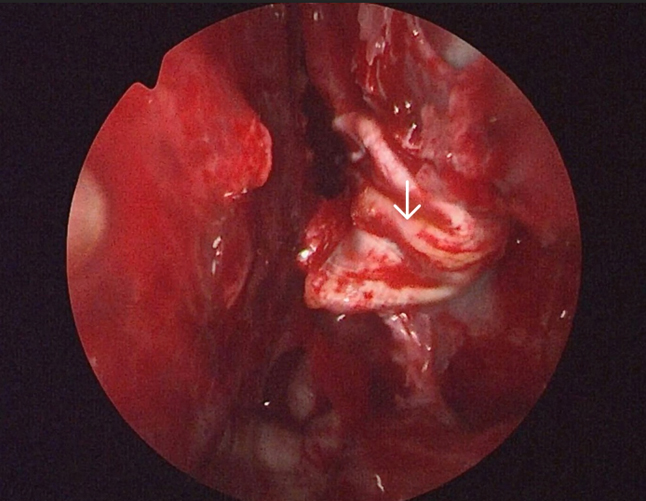

The meningoencephalocele was reduced by bipolar cauterization, the sphenoid sinus mucosa removed, the defect was closed by insertion of fat harvested from the left thigh (figure 7), followed by artificial dura, fascia lata harvested from the left thigh, followed by tissue glue and by another layer of fascia lata (figure 8). The defect in the cribriform plate was cauterised and sealed with fat and fascia lata harvested from the left thigh and subsequently reinforced with tissue glue and gel foam (figure 9).

Figure 7. Arrow showing the fat being placed on top of the sealed defect of the left lateral recess of sphenoid

Figure 8. Arrow showing fascia lata being draped on the fat-artificial dura layers for reinforcement of the defect